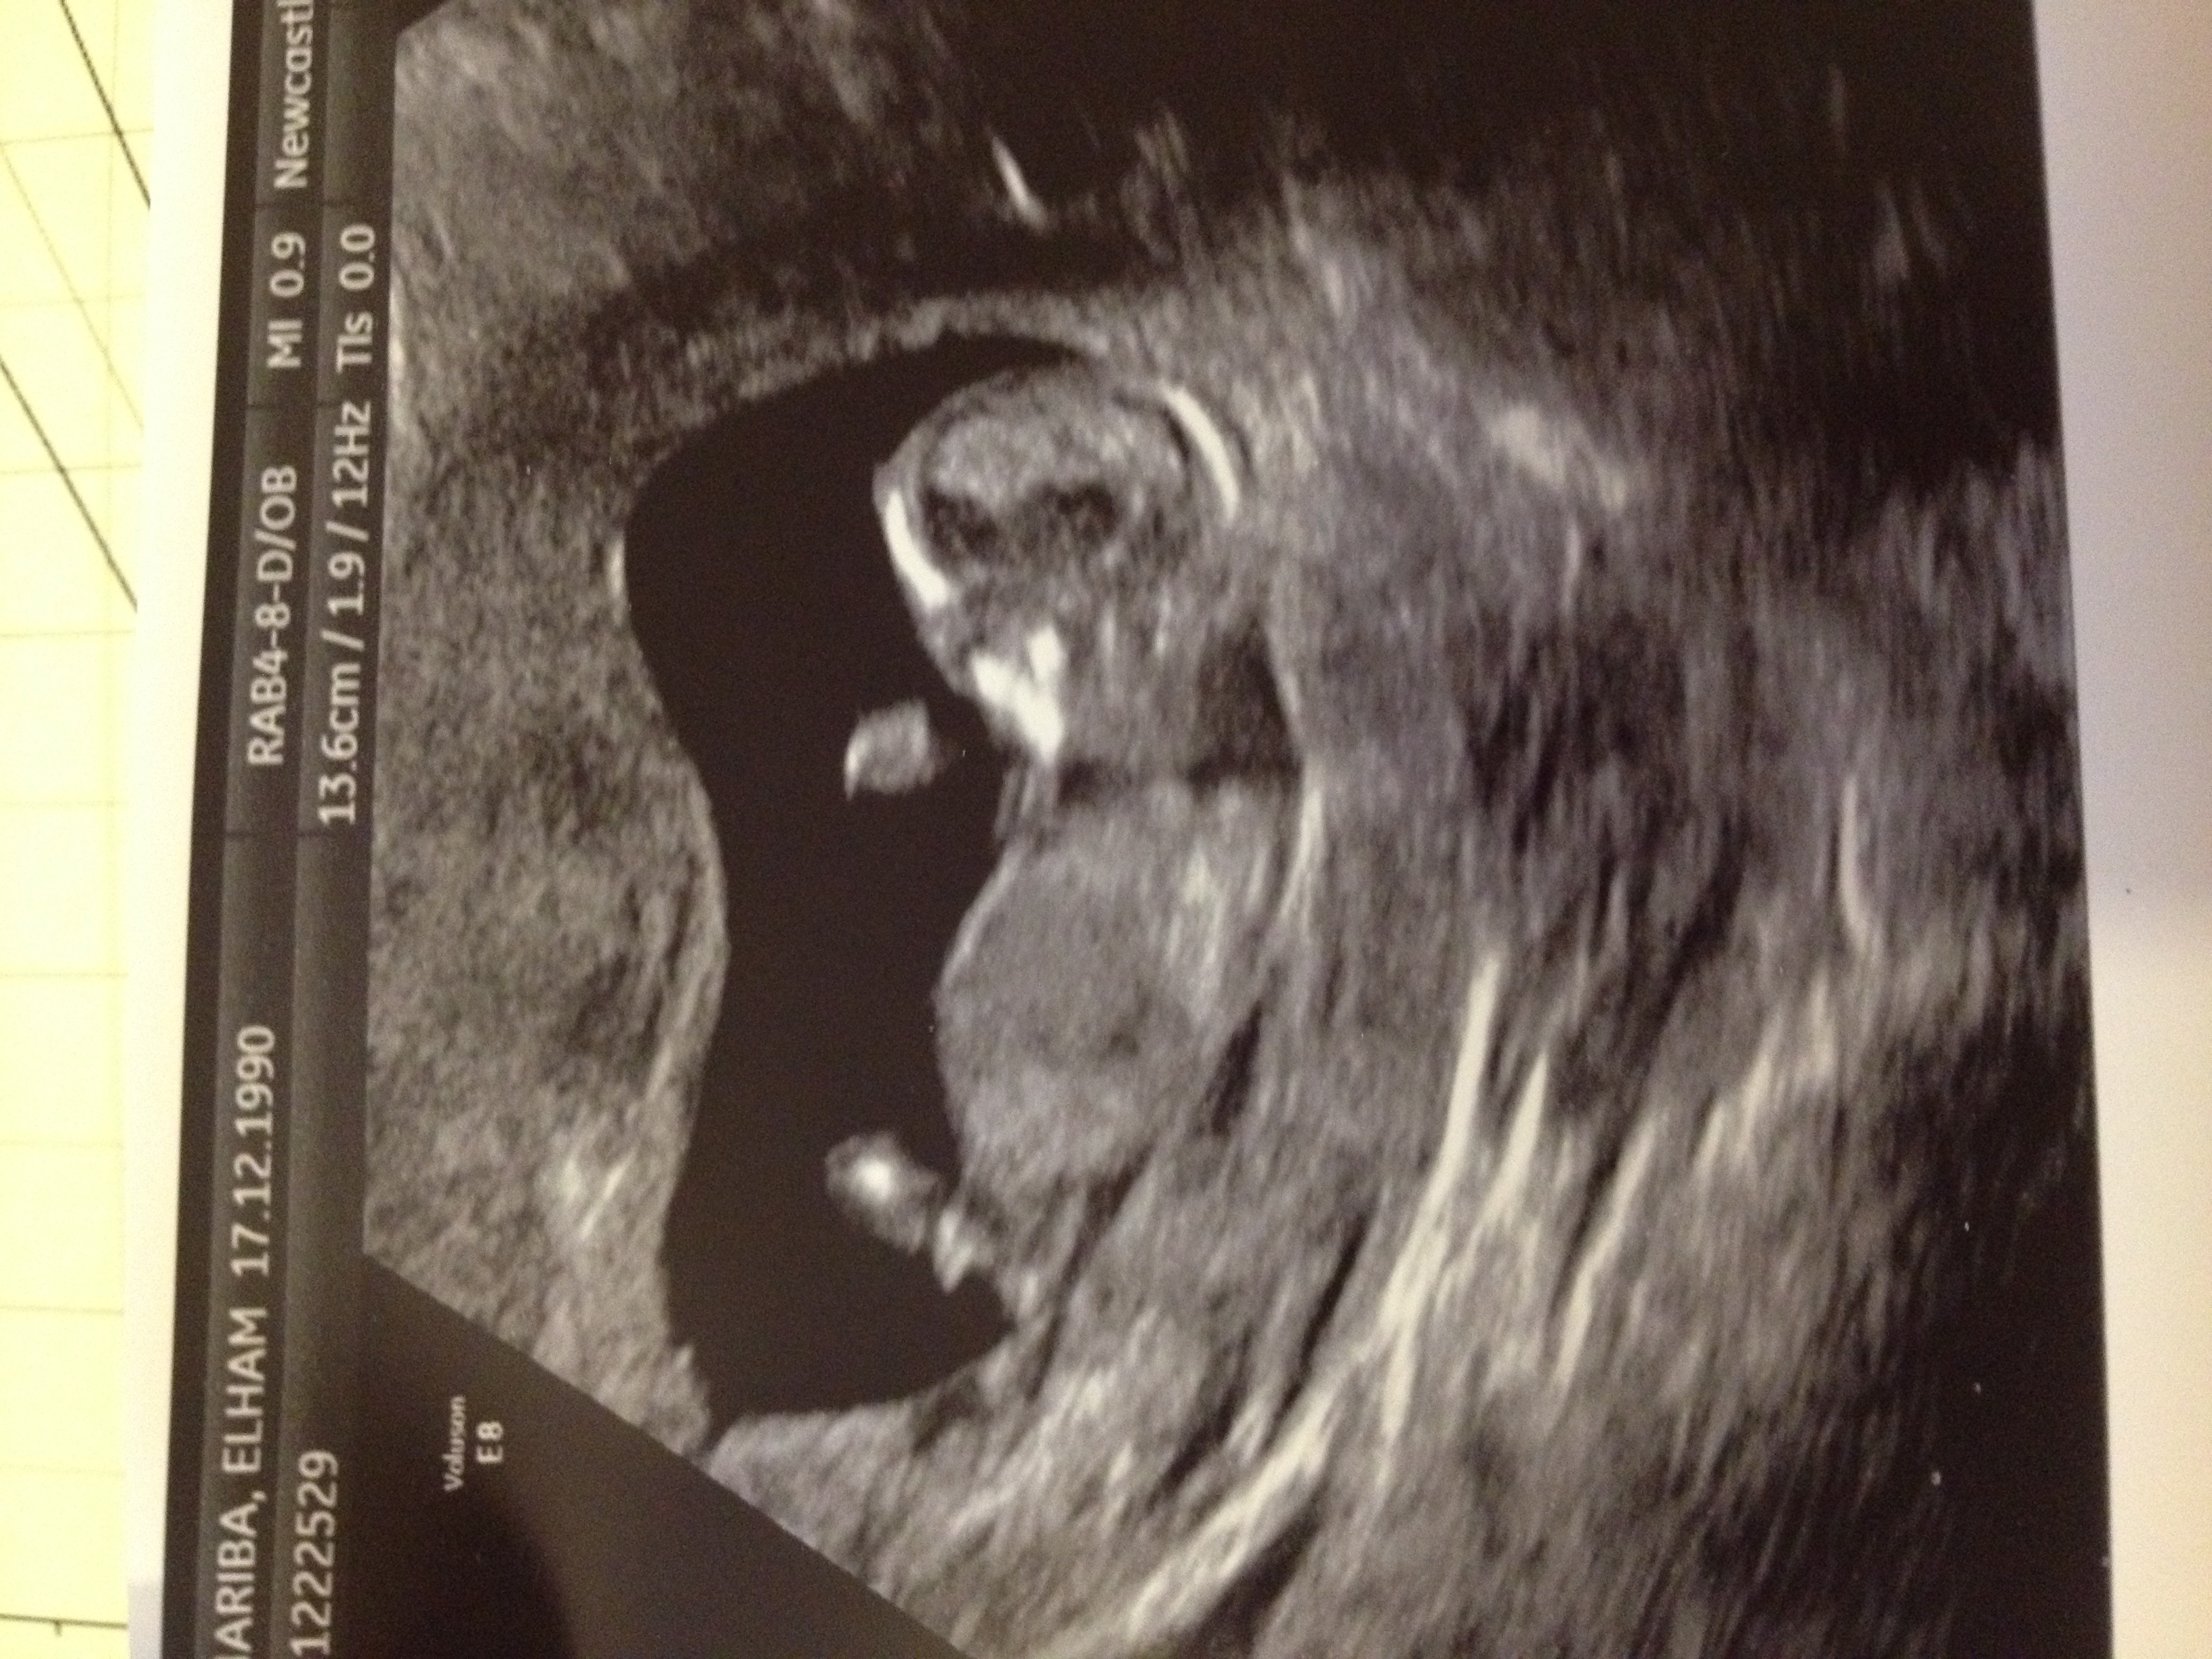

Sorry guys i added the pics now i was 12+3 at scan

No gender clues.

no clues, but i get a boy feeling.